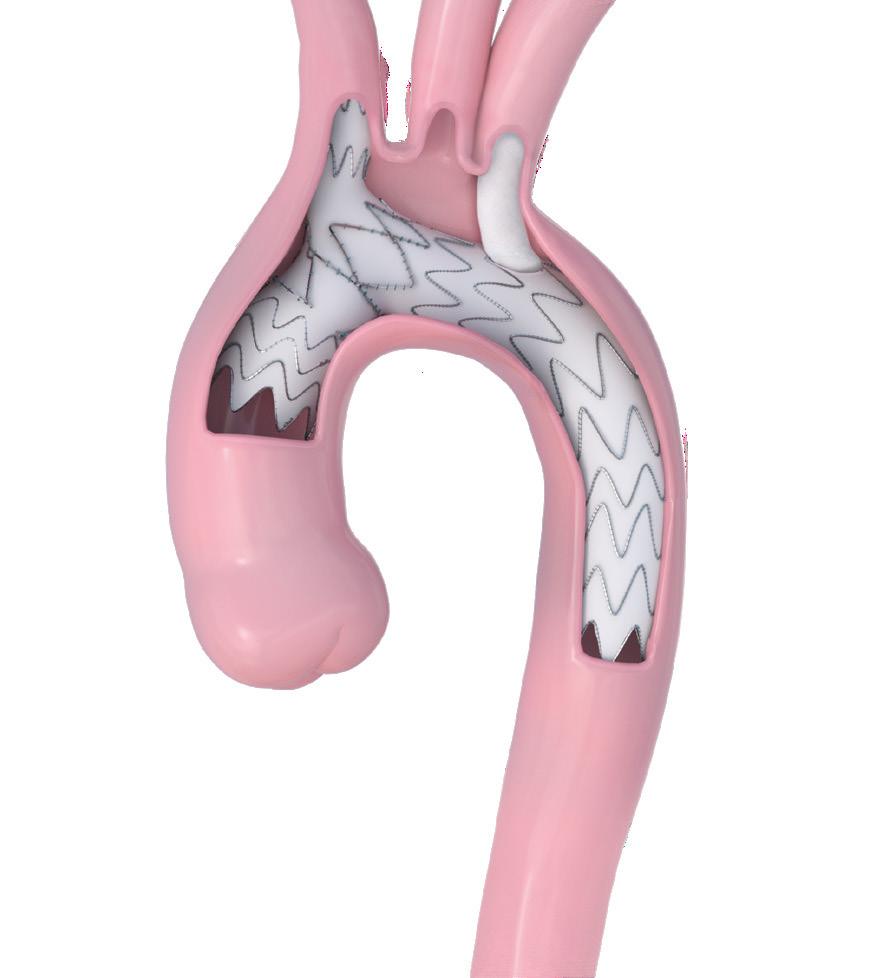

Additionally, ETAR can be more challenging as the visceral vessels are arduously cannulated from an upper body access due to the double angulation generated by current FET grafts (figure 1A-B). Here, we present a new custommade Thoraflex graft, named T-NEXT (Terumo Aortic, Inchinnan, Scotland), specifically designed to facilitate proximal and distal reinterventions (figure 2).

Unlike the conventional proximal-to-distal disposition of the neck-vessel branches, the T-NEXT graft features a distal and transverse arrangement of these branches. This design allows for a longer proximal graft segment, free from other prosthetic structures, and enables a more comfortable distal aortic clamping during root reintervention.

Additionally, this new branch arrangement provides a straight antegrade route for wires destined for upper access to the visceral vessels, simplifying ETAR (figures 2 C-D and 1). We believe the T-NEXT graft represents a promising advancement in FET surgery, addressing the limitations of current devices by facilitating both proximal aortic root and distal ETAR reinterventions.